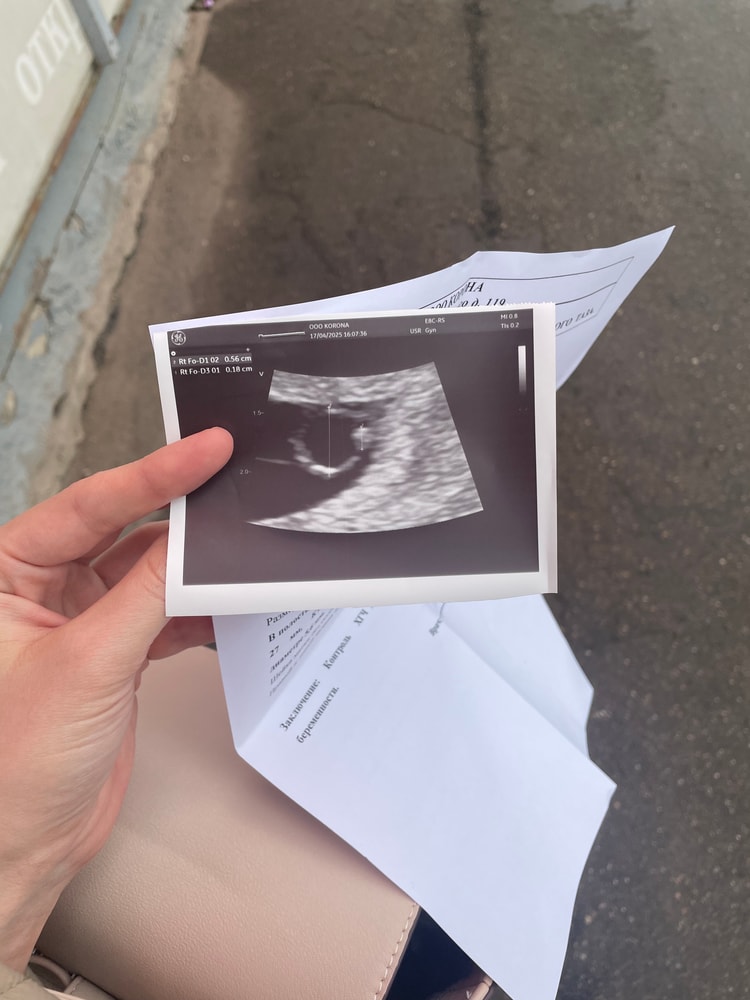

в прошлое воскресенье была на узи , срок 6+6 , эмбрион 1,4 мм, сб -

сходила сегодня (уже получается срок 7+3), эмбрион 1,8 мм, сб нет , но мы с врачом видели мерцание прям небольшое (она сказала уже должно быть на этом сроке отчетливое)

поставила замершую под вопросом, но сказала уже ничего хорошего не ждать

Наталья, вот и я смотрю что ктр очень маленький , и прирост за 4 дня на 4 мм

Валентина Стеблюк , не на 4 мм, а на 0,4 мм. В этом вся проблема. Это даже не рост, а погрешность измерения. А должен был быть уже около 6 мм.

Скажу честно, динамика не очень по росту эмбриона…пишу, потому что было почти один в один. На 5+6 ктр 1,2 мм через 10 дней на 7+1 2,9 мм и мерцание. Я все сразу поняла, хоть и нашли через 2 дня 111 чсс. Полная история у меня в дневнике, если интересно.

К сожалению замершая, эмбрион не растет,а хгч нет смысла сдавать,оно явно хорошо растет так как пя ваше 27 мм соответствует вашему акушерскому сроку,а вот эмбрион к сожалению нет,а хгч не имеет отношения к эмбриону,а пя и при зб расти может хорошо